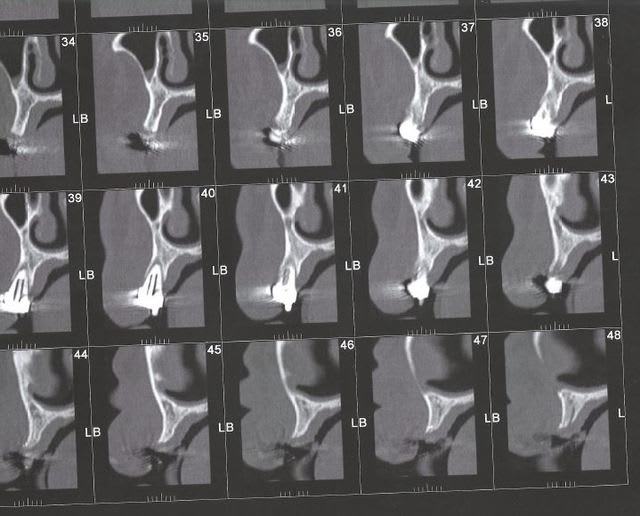

J'ai un patient qui souhaite faire une réhabilitation implantaire du maxillaire mais il refuse les sinus et les greffes.

Le problème, c'est qu'au vu du scan je pense pouvoir poser seulement trois implants (2 en secteur 1 et 1 en secteur).

Un quatrième secteur 2 juste avant la perte osseuse me semble très limite.

Je vous mets les scan en pj, si vous avez des idées (SANS GREFFE ni sinus au maximum ROG),je suis preneur.

Au niveau du secteur 2 , il y'avait un énorme kyste que j'ai prélevé et envoyé en biopsie (RAS) est-il possible d'imaginer une ROG avec les seules paroi osseuses latérales ???

maintenant ca a l'air pas si mal sur ton scan il faut mesurer, mais des 3X10 ca doit passer

Vers la coupe 82-83, y'aurait pas un petit espace exploitable ?